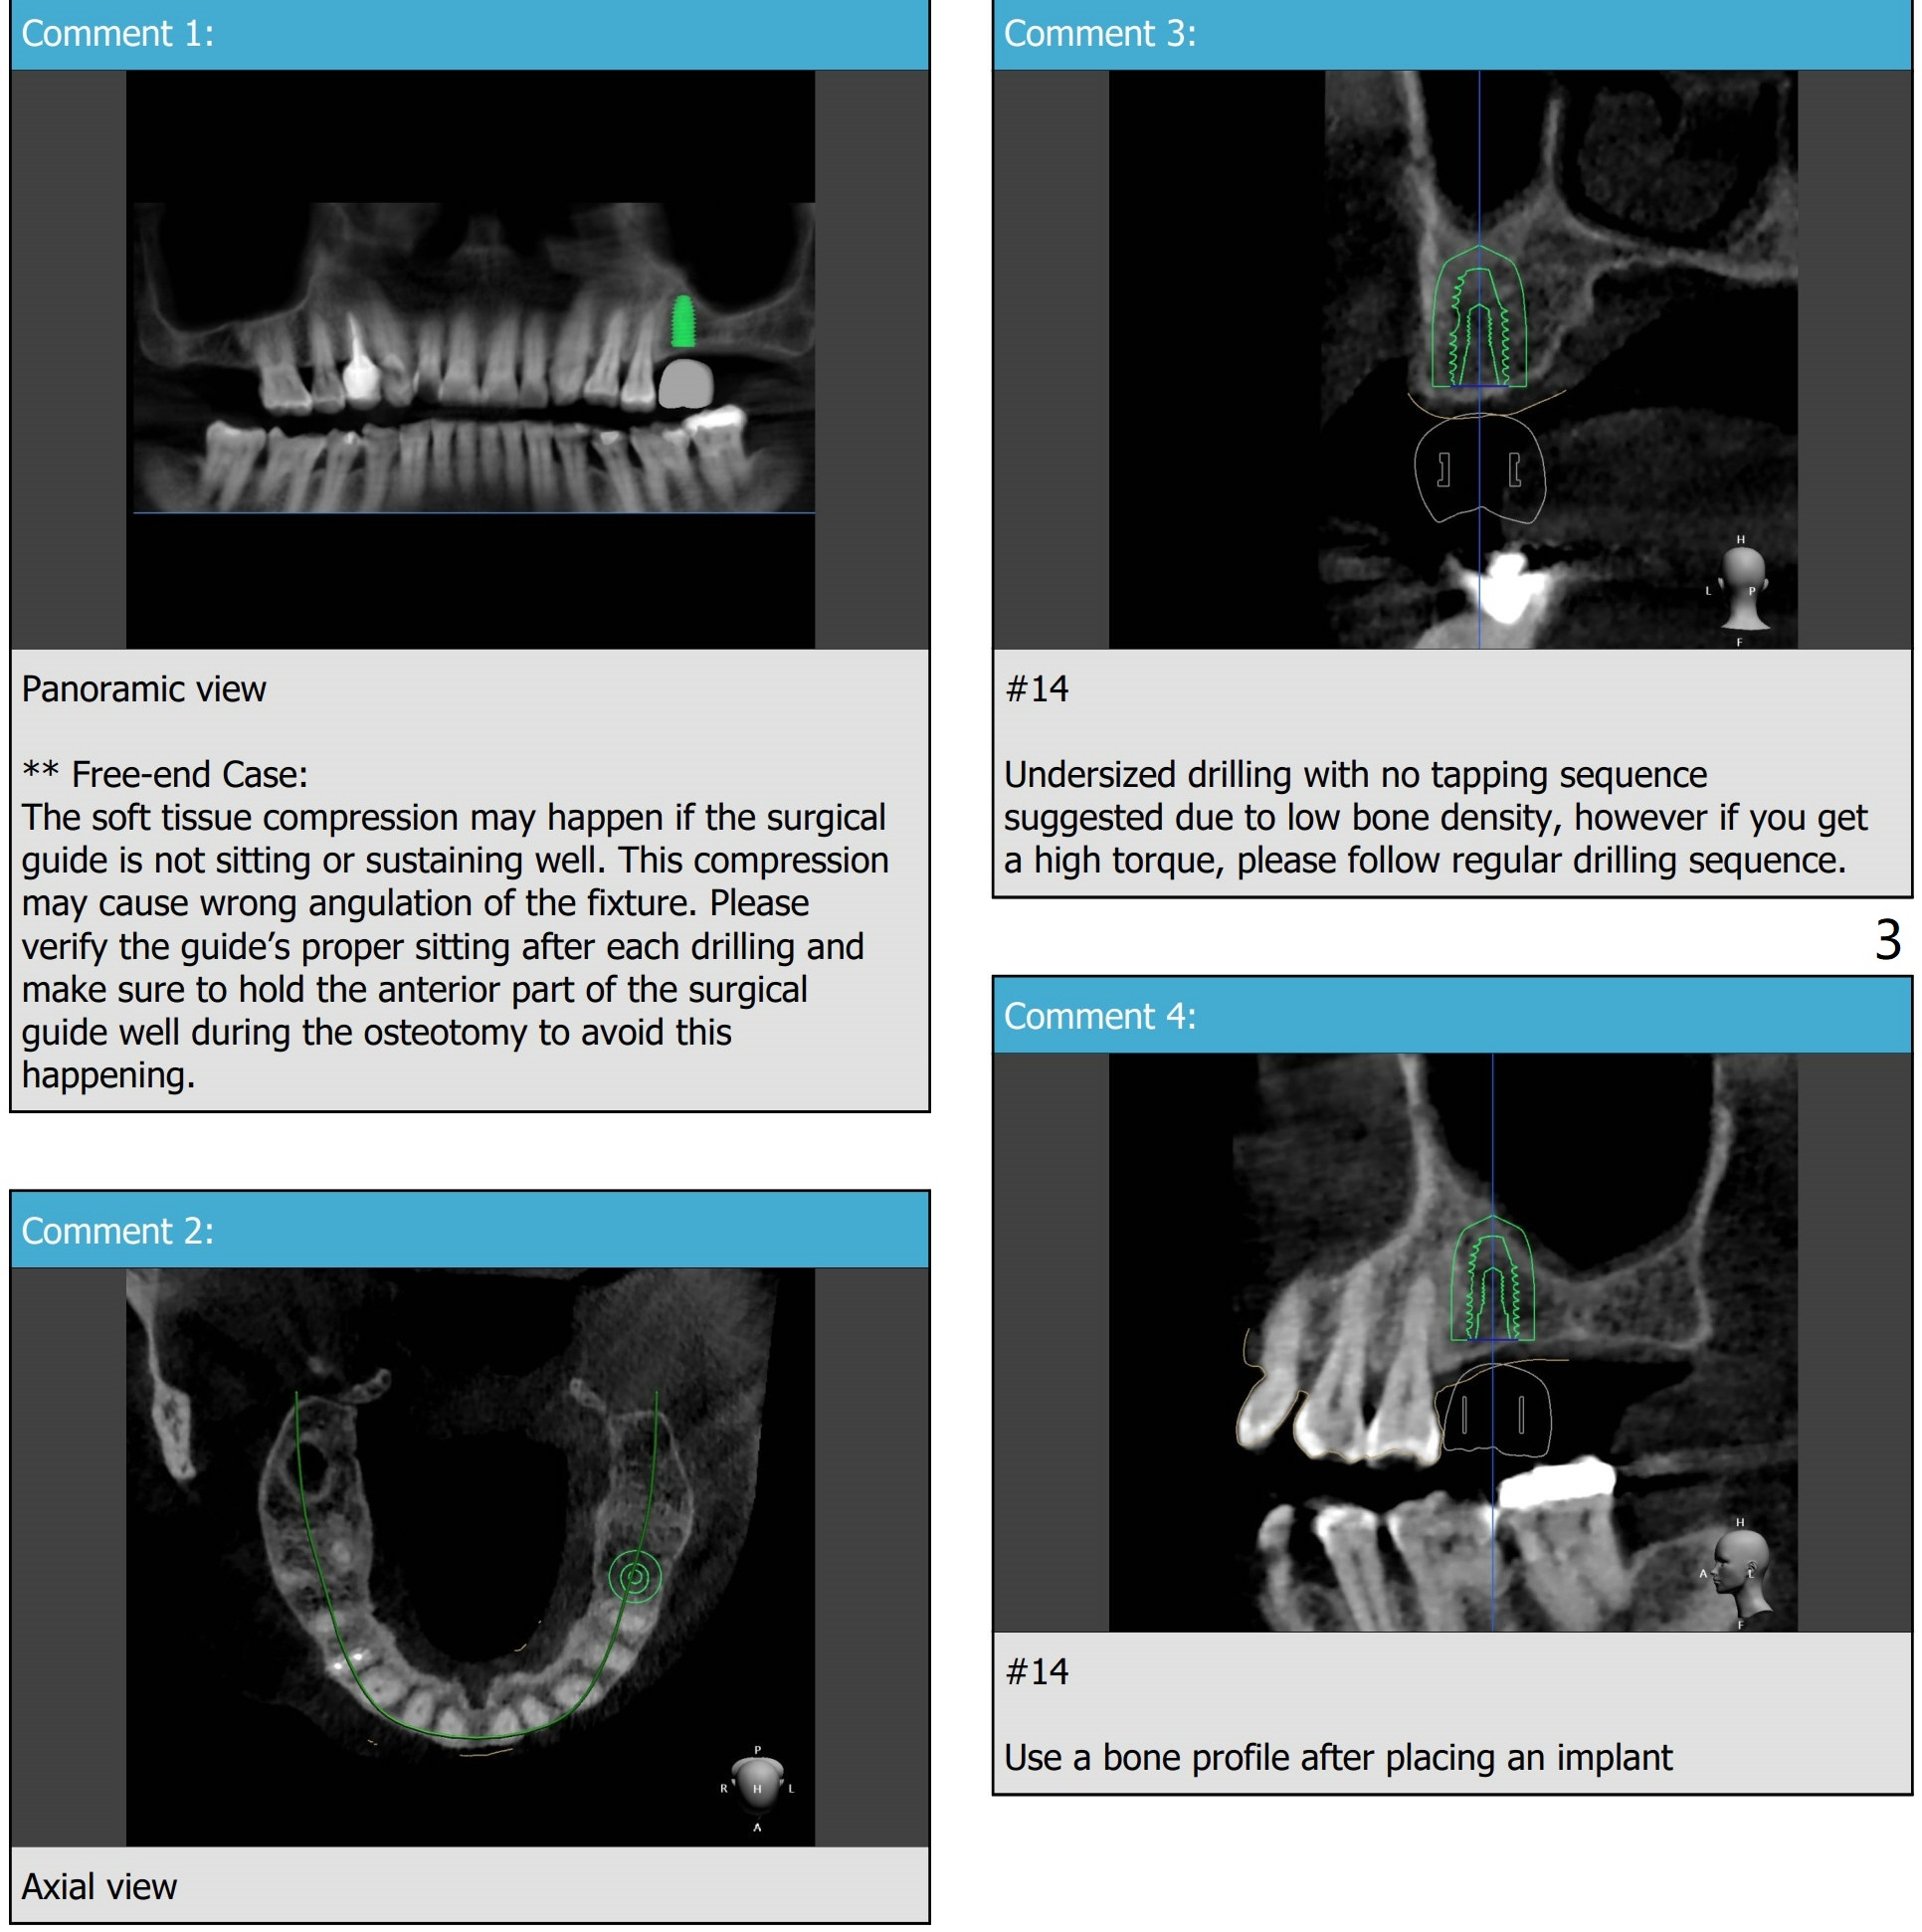

Low Bone Density

A 82-year-old woman requests implant at #14 with low bone density.